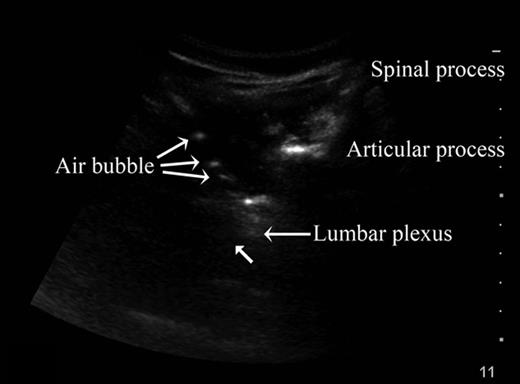

Images in #Anesthesiology: Ultrasound-guided #regionalAnesthesia micro air bubble contrast to visualize the needle. #peripheralNerveBlock #anesthesia #anaesthesia https://t.co/DO5lTAmoRB